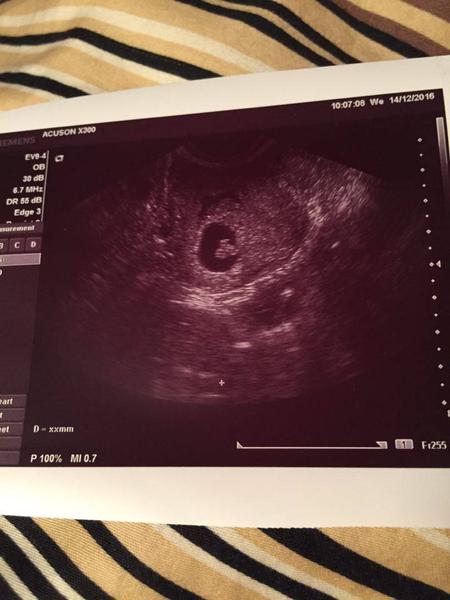

Holky, ja mluvim o trech bublinkach co jsou v ty nejvetsi cerny dutince? vidim nalevo fazolku a k ni priplaclou jednu bublinku 🙂 Co z toho by mel byt hematom? 🙂 Doktor nic takovyho nerikal 🙂

@bibianne dekuji! Velikost nevim, podle me gestacni vacek je cely ten cerny flek, ve kterem je to embryo se zloutkovym vackem? Ale nevim ani, jak velky byl minule, na tom asi nezalezi, spis na tom, jestli v nem neco je/neni videt. U me vypadal pred temi dvema tydny uplne prazdny a ted je tam tohle nadeleni 🙂